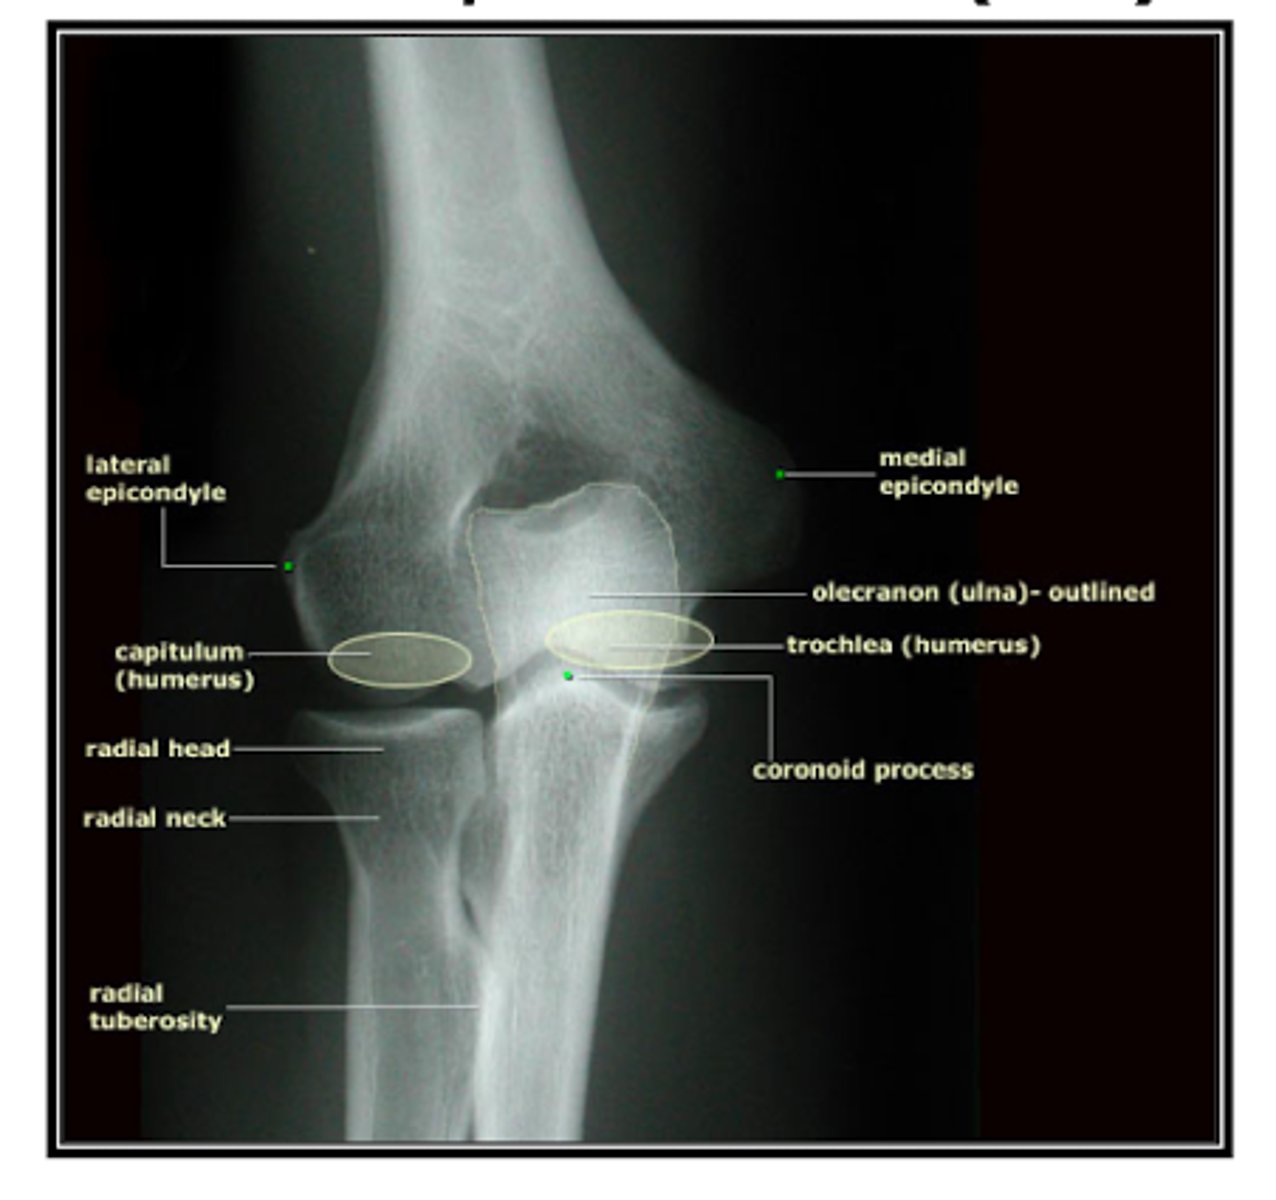

REVIEW: XR of elbow (AP view)